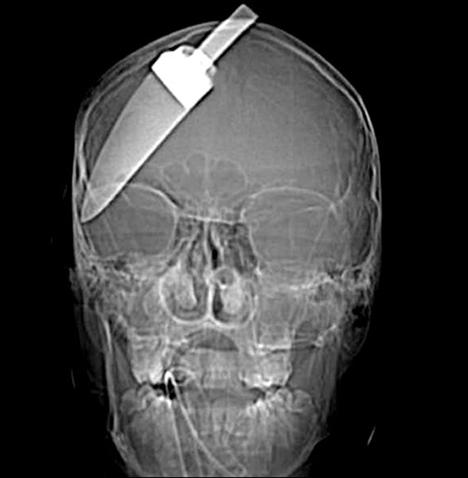

Şoke eden röntgen filmleri

Bu röntgen filmleri görenleri şaşkına çeviriyor!